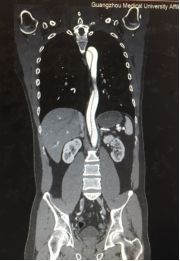

剧烈的疼痛让王先生有种说不出的恐惧感,他立即到当地医院紧急就诊。经过对症处理之后却不见效果,随后急转至广州医科大学附属第一医院急诊科。经过紧急胸腹部主动脉全程CT检查之后,诊断为主动脉夹层,随时可能破裂大出血,立即通过急诊绿色通道入住心血管内科。

在主动脉夹层的治疗方面,心血管内科常常采用介入的方式,但通过影像学资料分析,发现王先生血管里的这颗“炸弹”非常复杂:右侧锁骨下动脉竟然先天性开口异常,而夹层撕裂范围广泛,上至主动脉弓右侧迷走锁骨下动脉开口以远,下至双侧髂内、外动脉近端。

然而,为获得一个良好的支架着陆区、封住主动脉破口,如果仅仅通过植入覆膜支架封闭夹层会影响到双侧锁骨下动脉,从而使双上肢失去血液供应,可能会出现头晕、中风等后循环缺血症状。

结合王先生的实际情况,心血管内科黄铮主任认为,单纯的主动脉腔内隔绝术或联合“烟囱”技术等都不是该患者的最佳治疗方式,建议联合心脏外科一同会诊。经过心血管内科与心脏外科的专家会诊讨论之后,决定联手为王先生开展一场“杂交手术”——左锁骨下动脉转流+右锁骨下动脉转流+主动脉腔内隔绝术,一起拆除这颗不一般的“血管炸弹”。